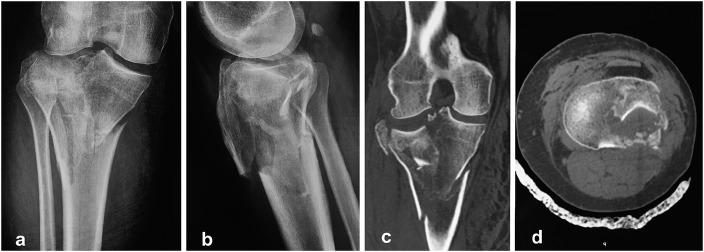

Bicondylar tibial plateau fractures have been treated with either plating or external fixation techniques, with conflicting results. A recently introduced technique involving the combined use of intramedullary nailing via a suprapatellar approach and condylar bolts could represent a new pathway toward better treatment of this severe injury.

The present report describes a retrospective and prospective study of all 17 patients (age range, 25 to 75 years) who were admitted under the author's care for the treatment of a closed, bicondylar tibial plateau fracture between 2013 and 2015. All patients consented to undergo fixation of the fracture with intramedullary nailing through a suprapatellar approach and with use of condylar bolts. The reconstructed articular surface was supported with freeze-dried allograft that had been previously soaked in concentrated bone marrow. The patients were followed at regular intervals, and the results were assessed with the Knee injury and Osteoarthritis Outcome Score (KOOS).

All patients were followed for at least 1 year (average and standard deviation, 25.23 ± 8.95 months; range, 12 to 46 months). All fractures united clinically and radiographically between 10 and 22 weeks (average, 15.1 ± 2.91 weeks), with no instances of neurovascular complication, infection, or implant failure. One patient underwent early revision of the fixation because of unsatisfactory reduction of the articular surface, and 1 patient had secondary fracture displacement. One condylar bolt was removed after fracture healing because of irritation at the insertion site. However, all patients regained knee motion without physiotherapy and all were fully weight-bearing by the fifth postoperative month.

双髁胫骨平台骨折的治疗方法有钢板固定或外固定技术,但结果存在争议。最近引入的一种技术,即通过髌上入路联合使用髓内钉和髁螺栓,可能为更好地治疗这种严重损伤开辟一条新途径。

本报告描述了一项回顾性和前瞻性研究,研究对象为2013年至2015年间在作者治疗下因闭合性双髁胫骨平台骨折入院的所有17例患者(年龄范围25至75岁)。所有患者均同意采用髌上入路髓内钉固定并使用髁螺栓固定骨折。用预先浸泡在浓缩骨髓中的冻干同种异体骨支撑重建的关节面。定期对患者进行随访,并采用膝关节损伤和骨关节炎疗效评分(KOOS)评估结果。

所有患者均随访至少1年(平均和标准差,25.23±8.95个月;范围,12至46个月)。所有骨折在10至22周(平均,15.1±2.91周)临床和影像学上均愈合,无神经血管并发症、感染或植入物失败的情况。1例患者因关节面复位不满意而早期进行了内固定翻修,1例患者出现二次骨折移位。1枚髁螺栓在骨折愈合后因插入部位刺激而取出。然而,所有患者未经物理治疗即恢复了膝关节活动,且在术后第五个月时均完全负重。